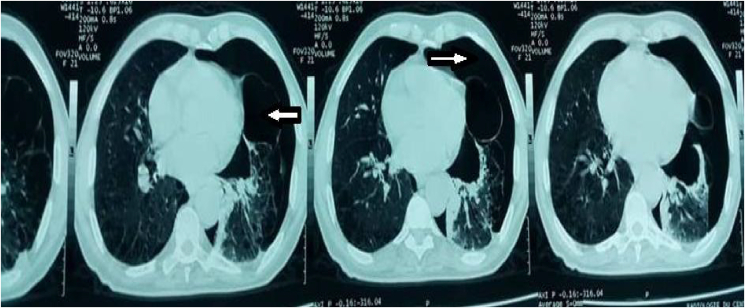

The abdominal and chest x-ray showed an emphysematous left lung with pneumothorax of the same side of 57%. CT chest to objectify a big ball of emphysema and pneumothorax of great abundance (Fig. 3).

Fig. 3.

CT demonstrates left pneumo-haemothorax with a ball of emphysema.